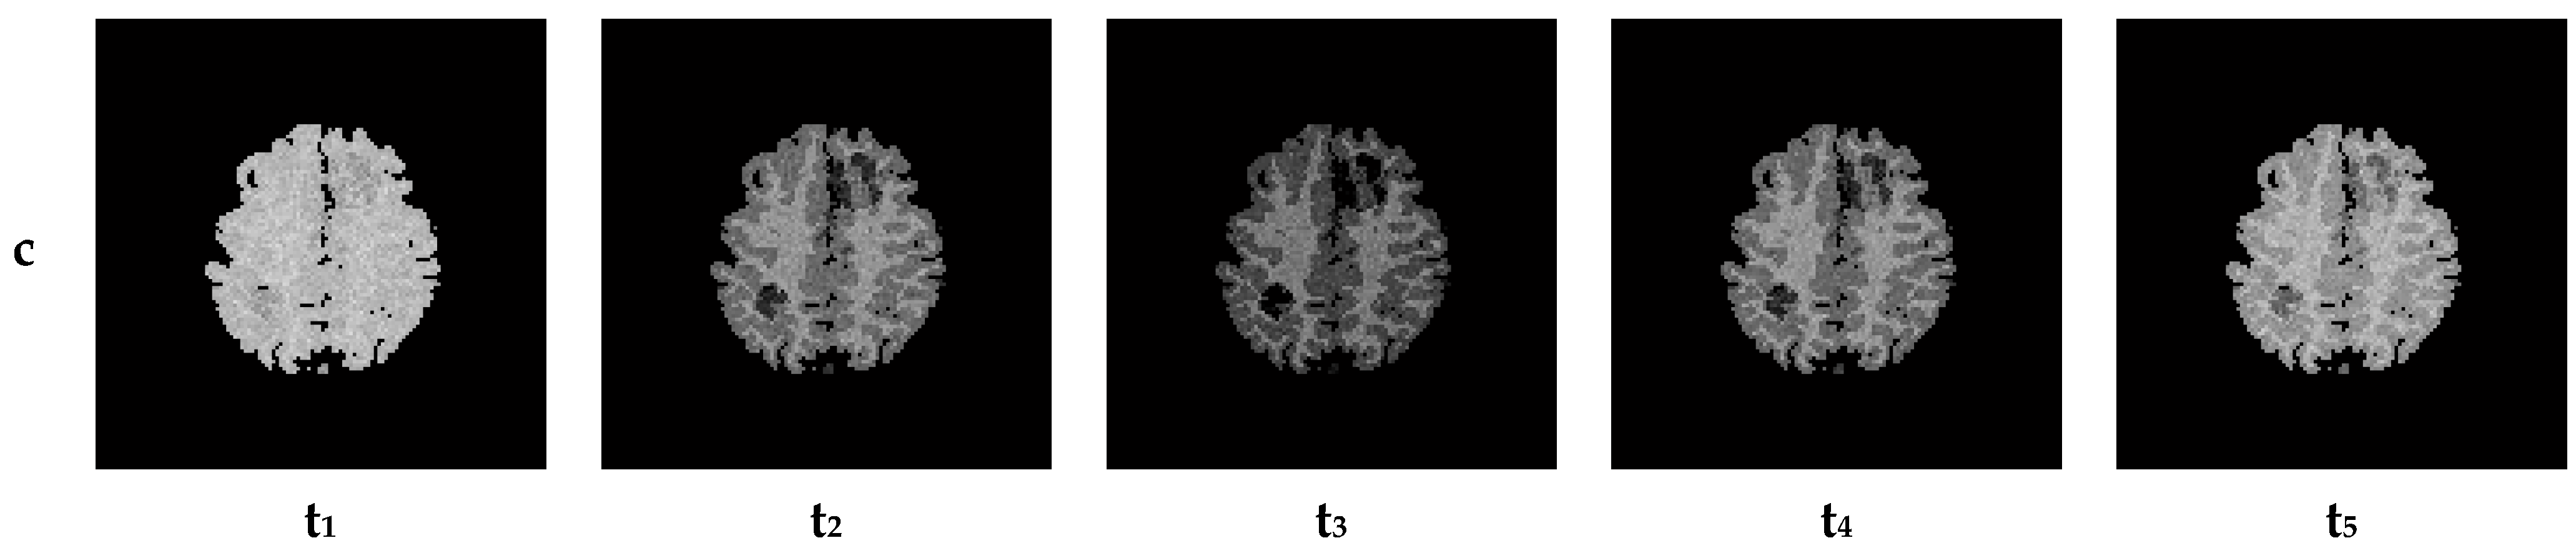

7. Results—Exemplary DSC-MRI Study Models